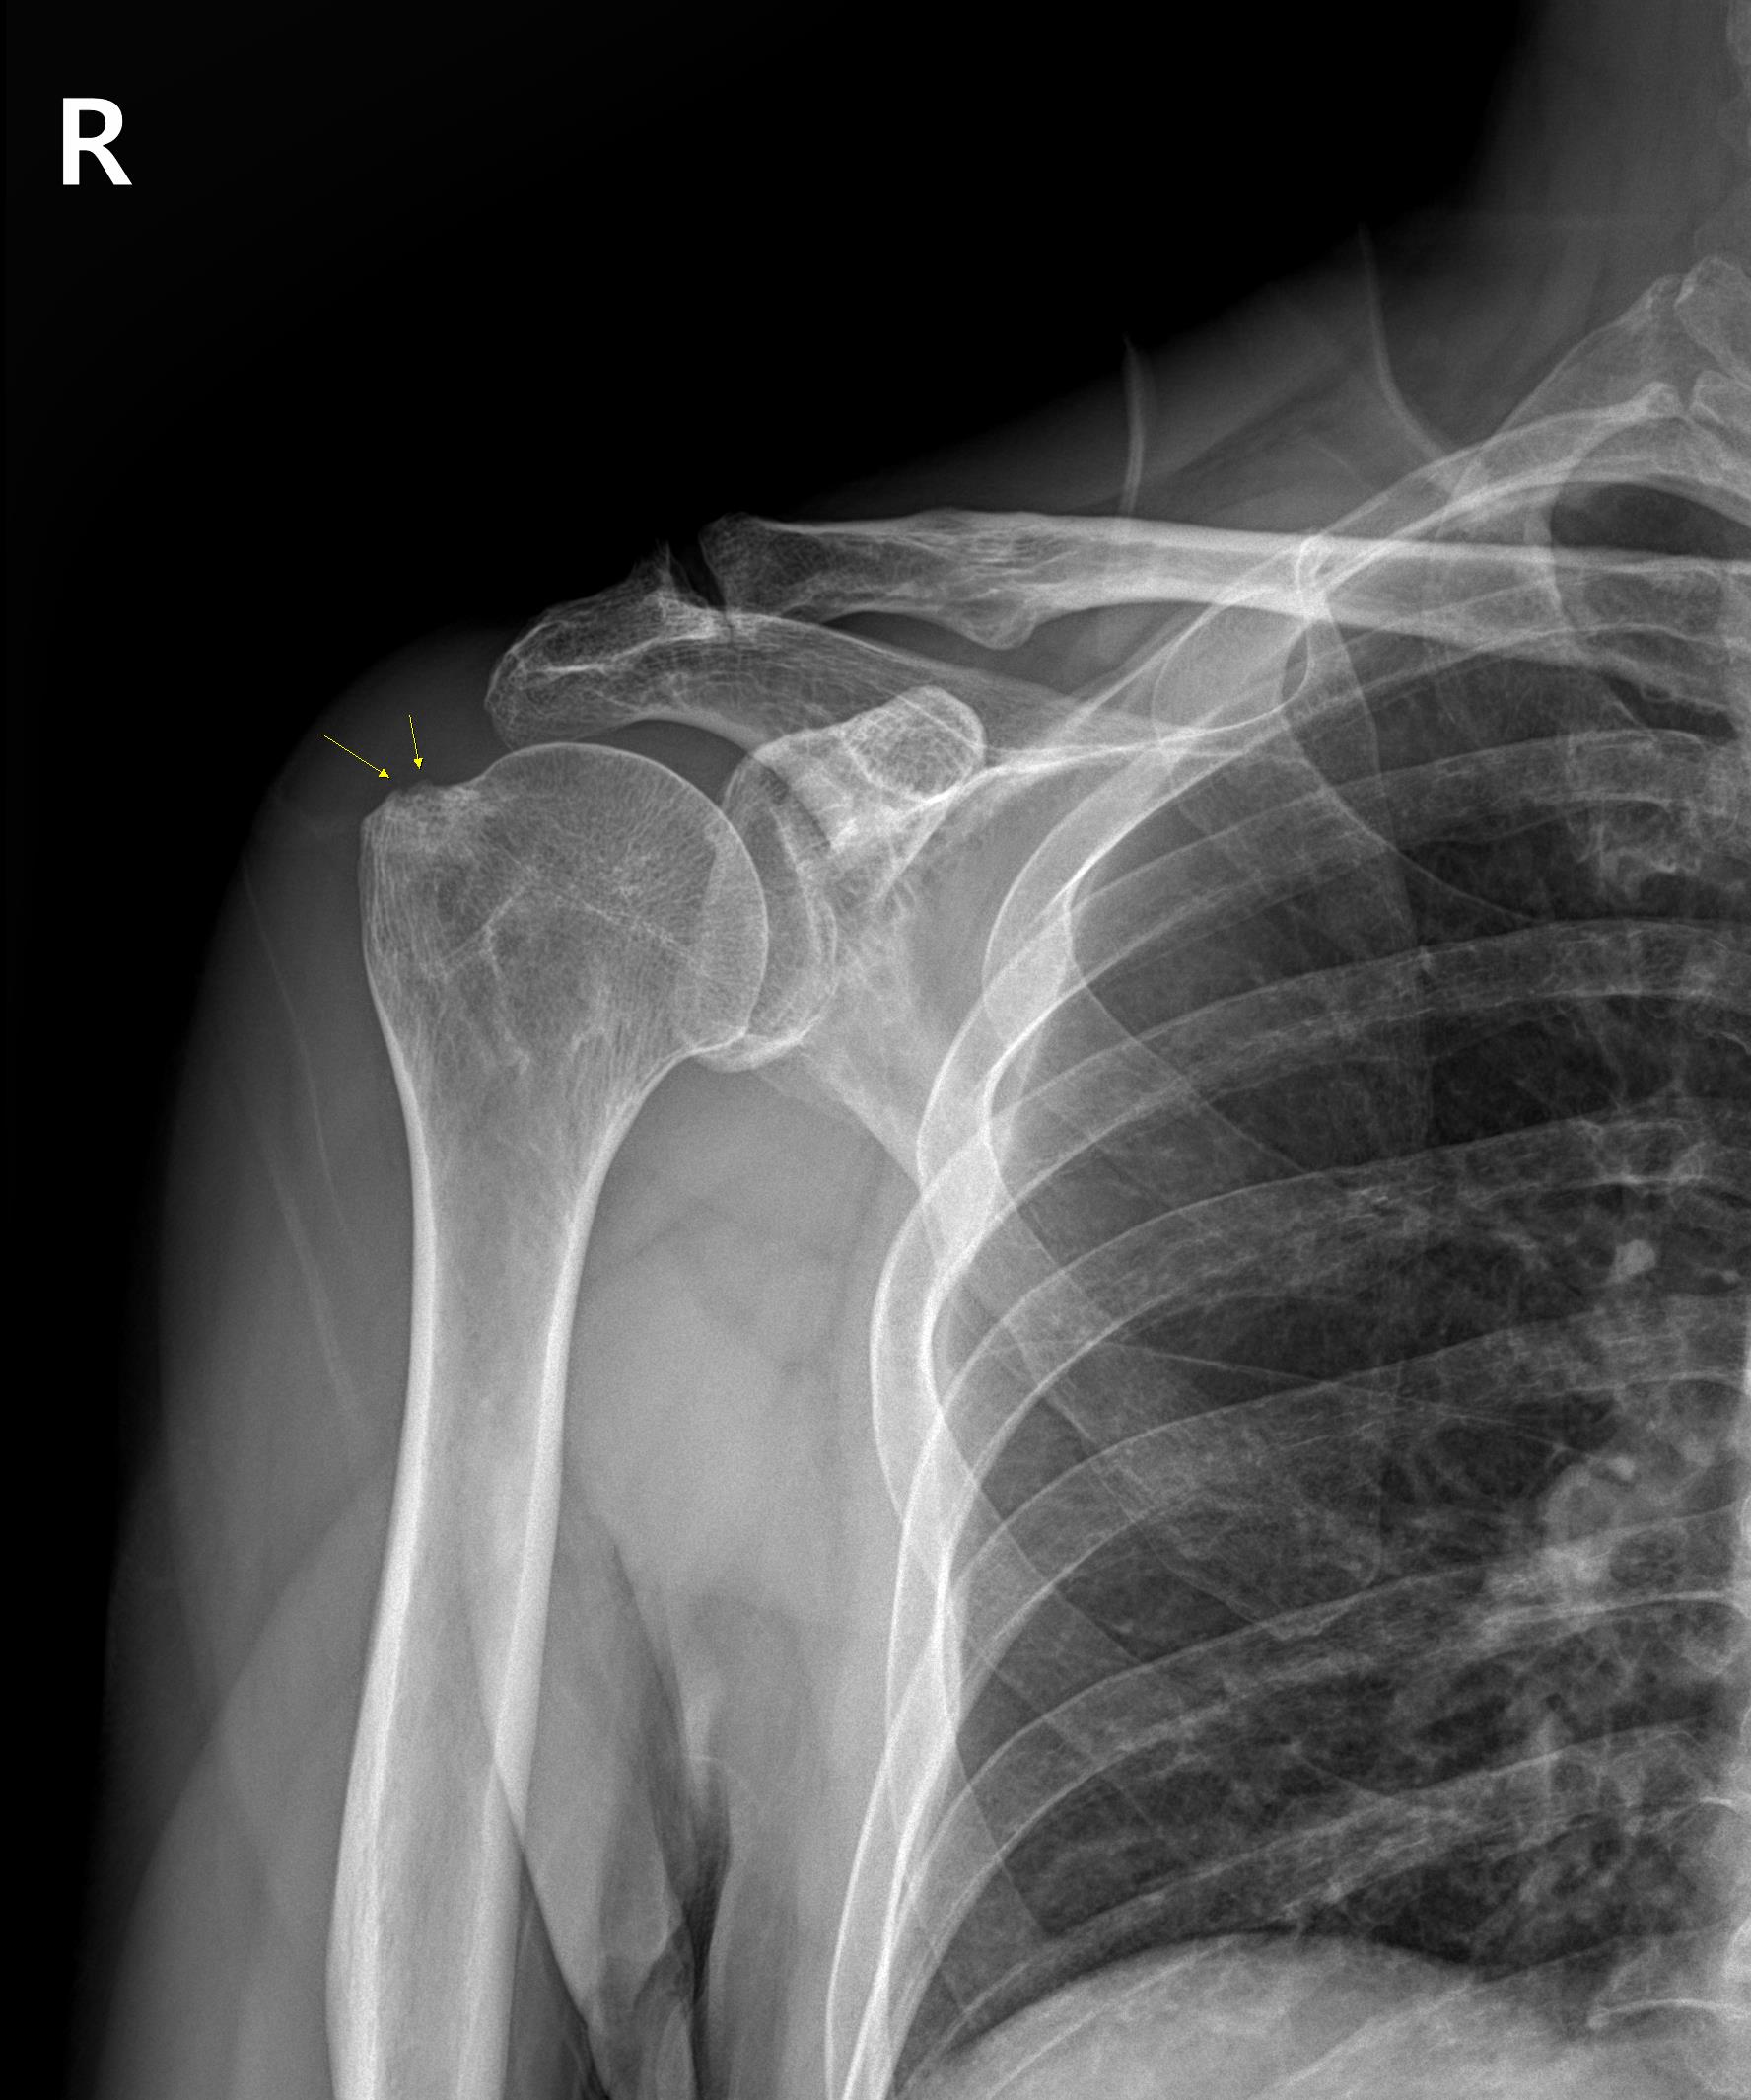

x-ray 결과는....

골절이나 석회는 아니지만 뼈의 라인이 좀 울퉁불퉁한 소견을 보이네요. 이걸 골극(bone spur)라고 하는데요. 염증이라던지 등등...의 문제가 오래 반복되면 그 부위의 뼈가 지저분해지는 소견이 보입니다. 예를들면 무릎의 퇴행성 관절염이 진행되면 그 부위의 뼈가 튀어나면서 지저분해지는 거죠.

골극이 보인다는건 어떤 문제가 생긴지 좀 오래 되었다는걸 말합니다.